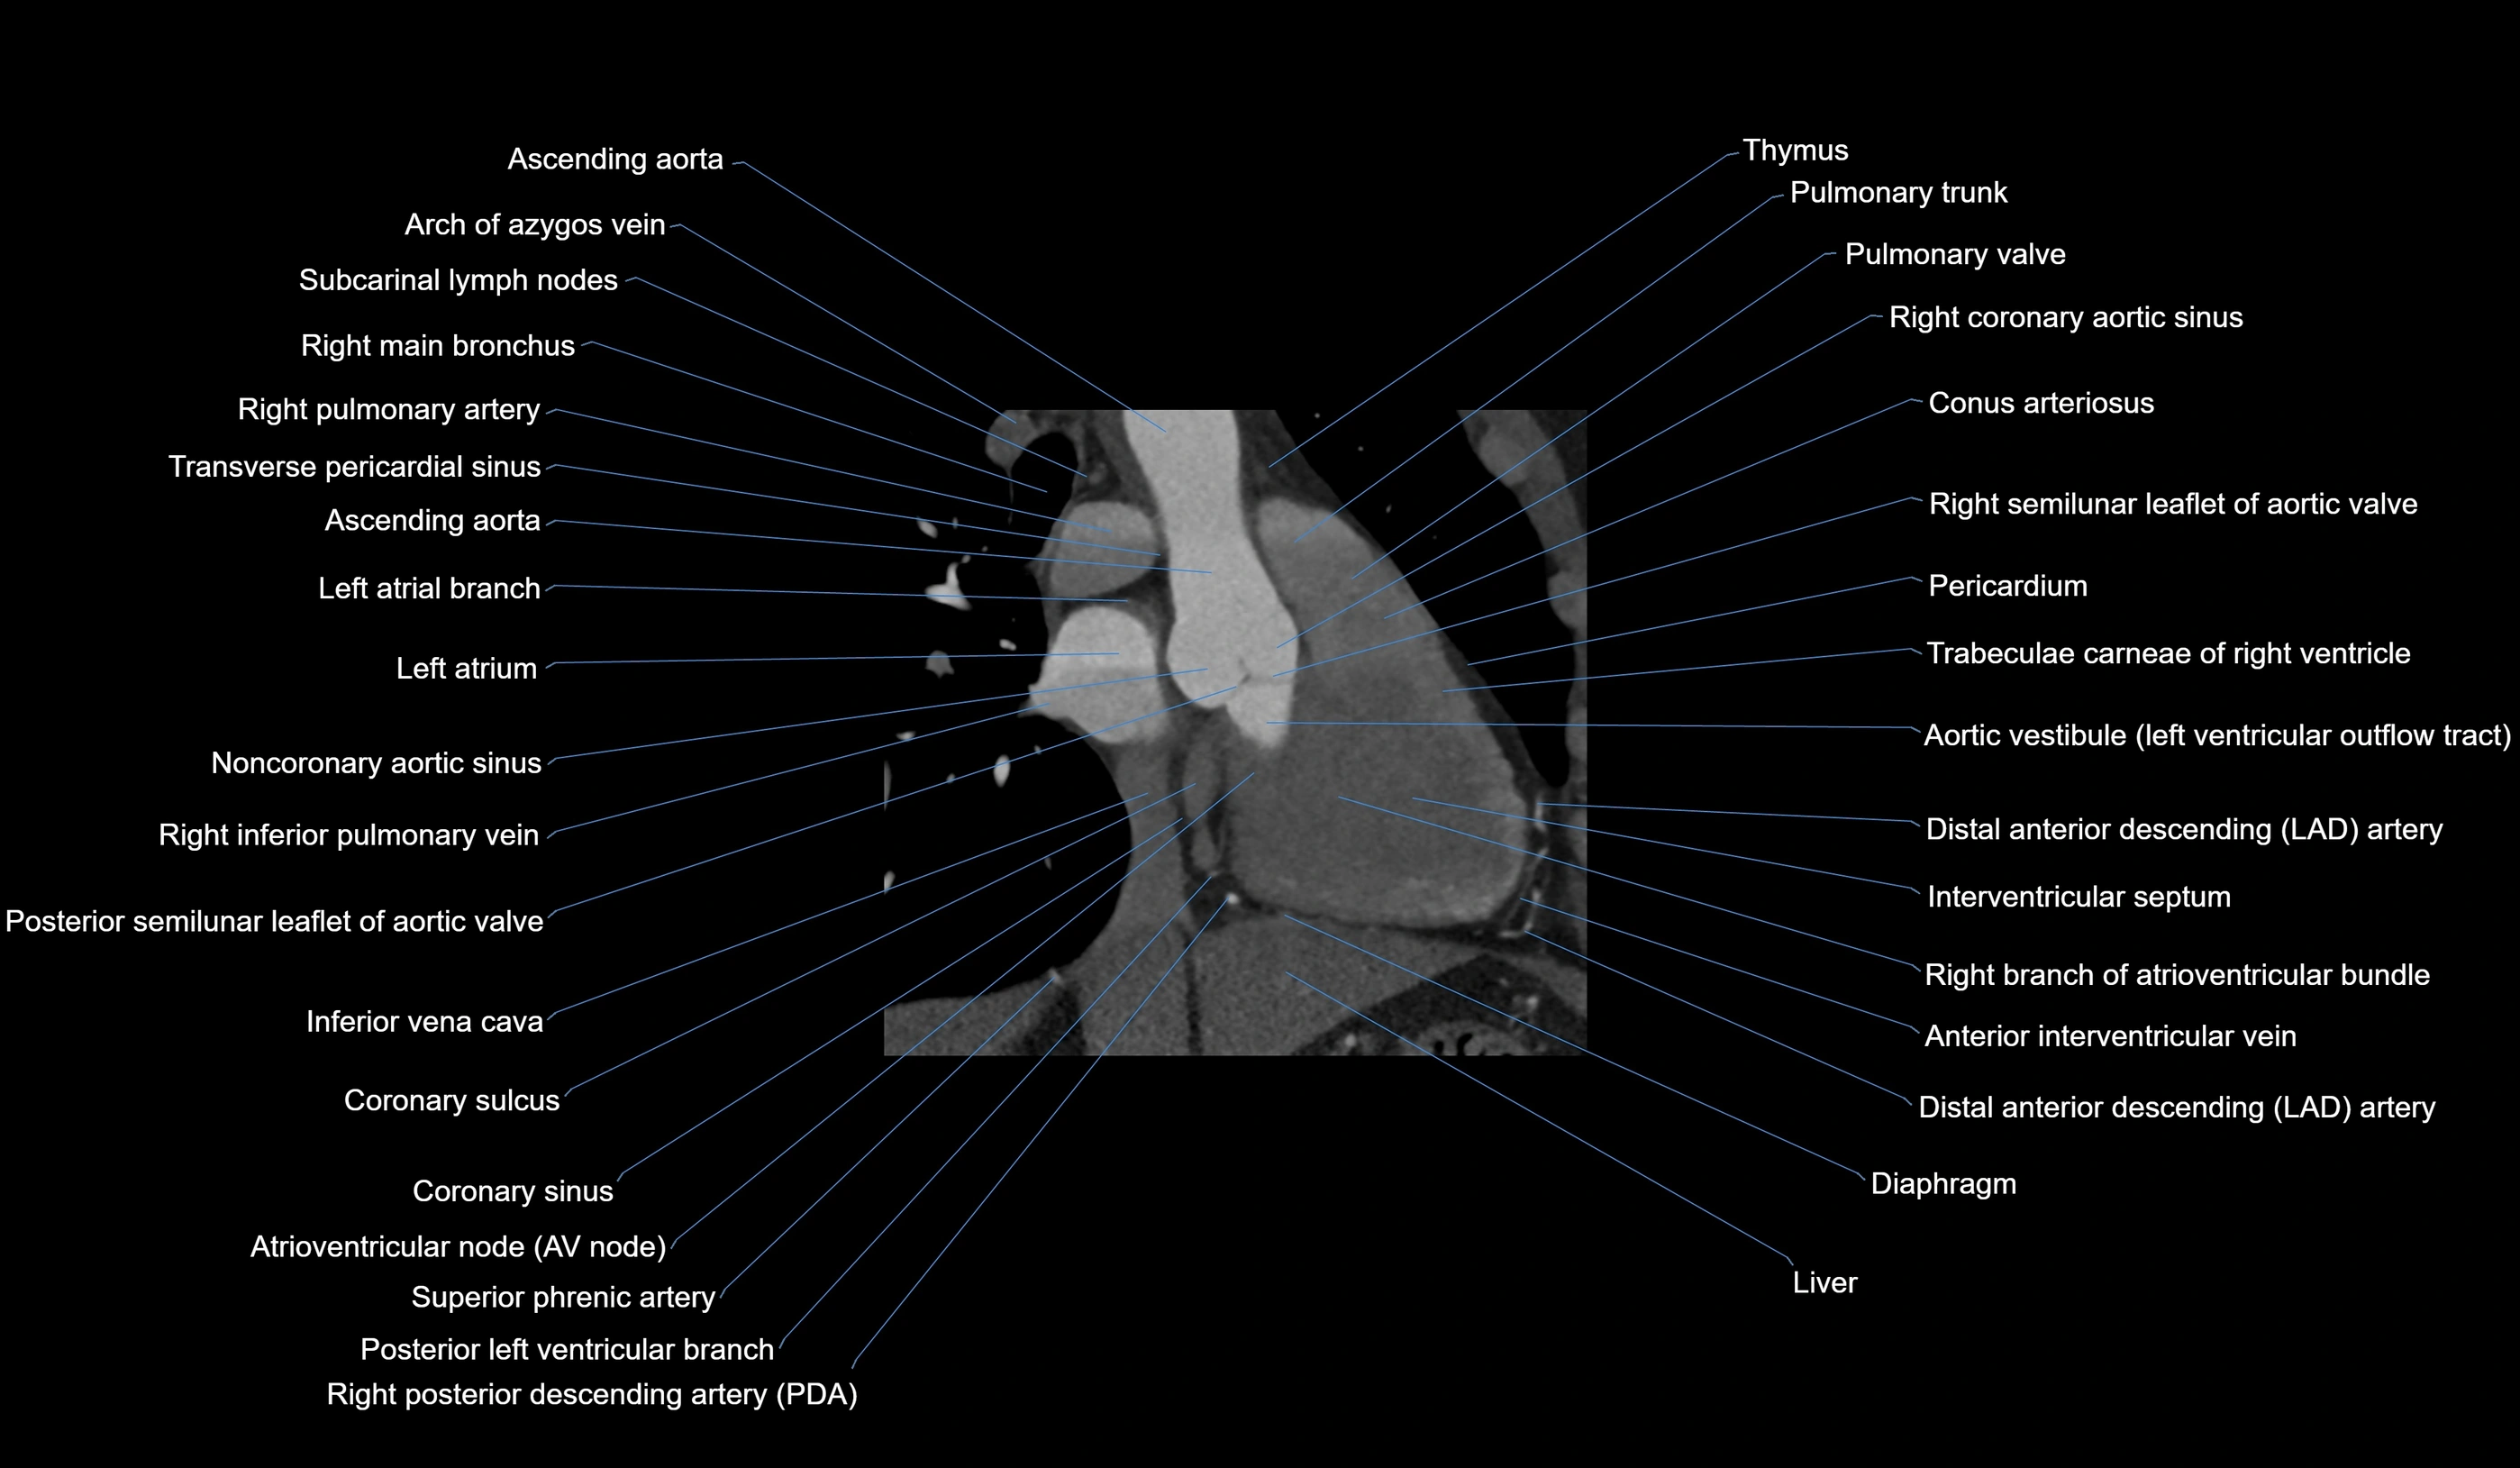

CT Appearance

Non-contrast CT (Calcium Scoring):

-

AM artery visualized for coronary calcium scoring

Calcified plaques appear as hyperdense foci; scored with Agatston method

CT Coronary Angiography (CCTA):

Best non-invasive modality for acute marginal artery visualization

Shows origin, course along the acute margin, and right ventricular branches

Detects stenosis, occlusion, calcified and non-calcified plaques, aneurysm, or anomalous course

Multiplanar reformats and 3D reconstructions help in pre-PCI and surgical planning

Critical for assessing right ventricular infarction risk in RCA disease

MRI image

CT images